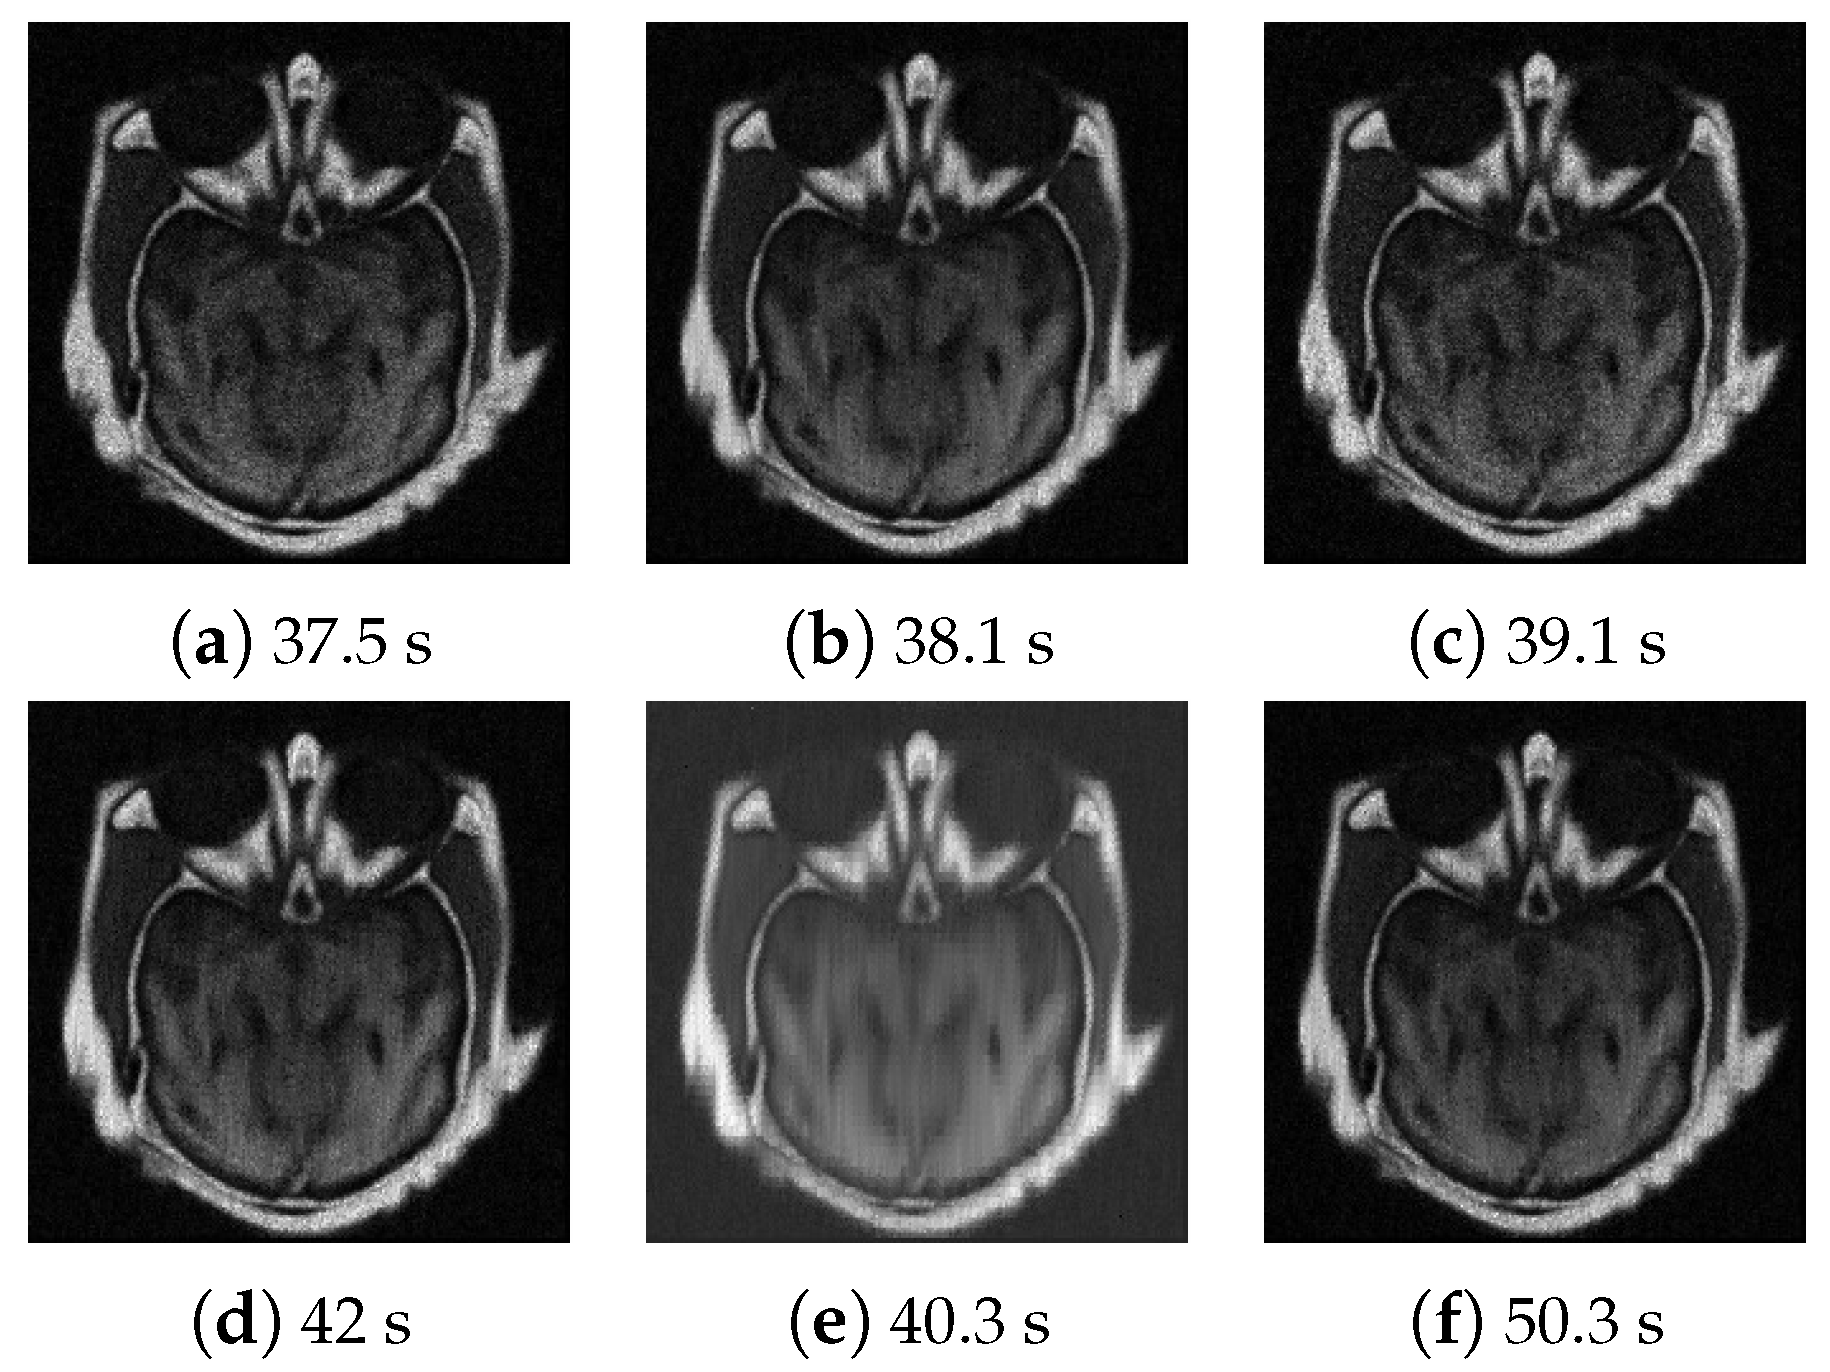

4.3. Numerical Experimental Results and Analysis